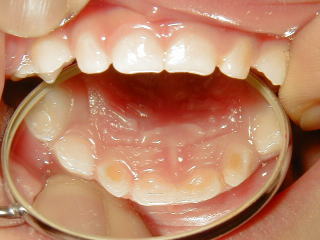

1歳から1歳半までの間、唾液の流れの少ない状態で夜間母乳が入ると、上の前歯の裏側に乳汁が停滞してその場所からむし歯が出来てくると考えています。

夜間授乳が1回程度なら、被害の程度も軽症なので、再石灰化してむし歯にまで進むことはありません。

しかし、3~4回以上の回数の夜間授乳があると、再石灰化が追い付かずむし歯になってしまいます。